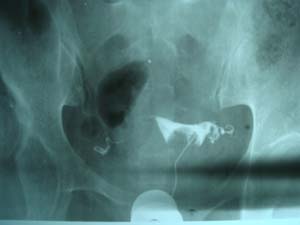

双侧输卵管是通的。

子宫输卵管造影未见明确异常。

子宫腔光整,双侧输卵管通畅,盆腔内造影剂弥散可。

各位子宫内是有个圆形充盈缺损,子宫呈倒“三角形”形态没有完全被造影剂充盈呀。子宫肌瘤。应该在拍两张斜位就好了 。

子宫体确有充盈缺损。考虑子宫肌瘤。子宫左倾

子宫输卵管造影未见明显异常,宫内充盈负影为气囊压迫所致。